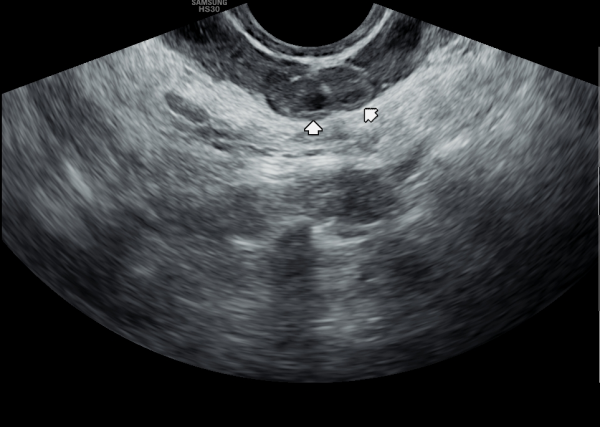

서울가정의학과의원에 첫 내원 당일 지난 5개월동안 회음부 통증과 배뇨장애로 타 비뇨기과 여러곳에서 치료를 했으나 증상의 호전이 없다고 내원 당일 검사한 경직장 전립선 초음파 검사상 사정관 입구의 석회화와 사정관의 섬유화 그리고 정낭의 낭종이 관찰되는 초음파 자료입니다.

On the first visit to Seoul Family Medicine Clinic, the patient reported having perineal pain and urination problems for the past five months, despite receiving treatment at several other urology clinics with no improvement.

A transrectal prostate ultrasound performed on the day of the visit showed calcification at the opening of the ejaculatory duct, fibrosis (scarring) of the duct itself, and cysts in the seminal vesicles.

또한 방광벽이 배뇨장애로 두꺼워져 과민성 방광이 의심되는 초음파 사진입니다.

The ultrasound image also shows that the bladder wall has become thickened, likely due to urination difficulties. This may suggest an overactive bladder, which can cause frequent or urgent urination.